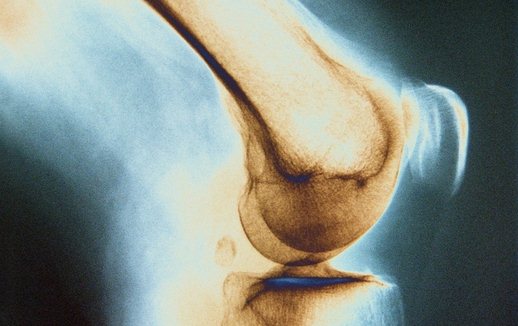

Наиболее характерные симптомы туберкулеза костей – это припухлость в области пораженного сустава, атрофия мягких тканей, скопление серозного или серозно-фибринозиого экссудата, мышечная контрактура и ограничение подвижности суставной части. При рентгенологическом исследовании выявляются: ограниченные полости в кости, разрежение костного вещества и расширение или сужение суставной щели (зависит от наличия экссудата).